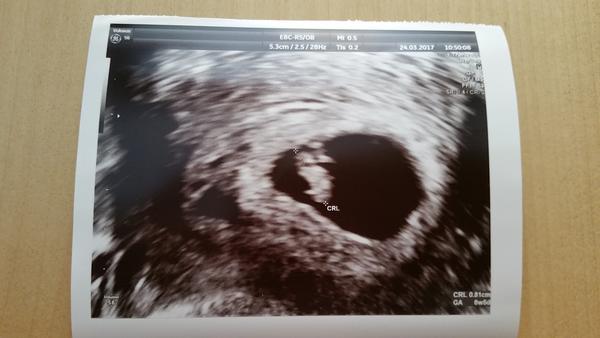

Ahoj holky, moc děkuji za podporu. Kontrola dobré, srdíčko bije, mám radost. Další ko mi dala za 14 dní, říkala, že na odběry a screening za 5 týdnů, tak že by to bylo moc za dlouho, tak mám ještě za dva týdny přijít. Jinak podle UTZ jsem 6+5, podle MS 7+0 🙂. Přikládám tu moji skvrnku 🙂